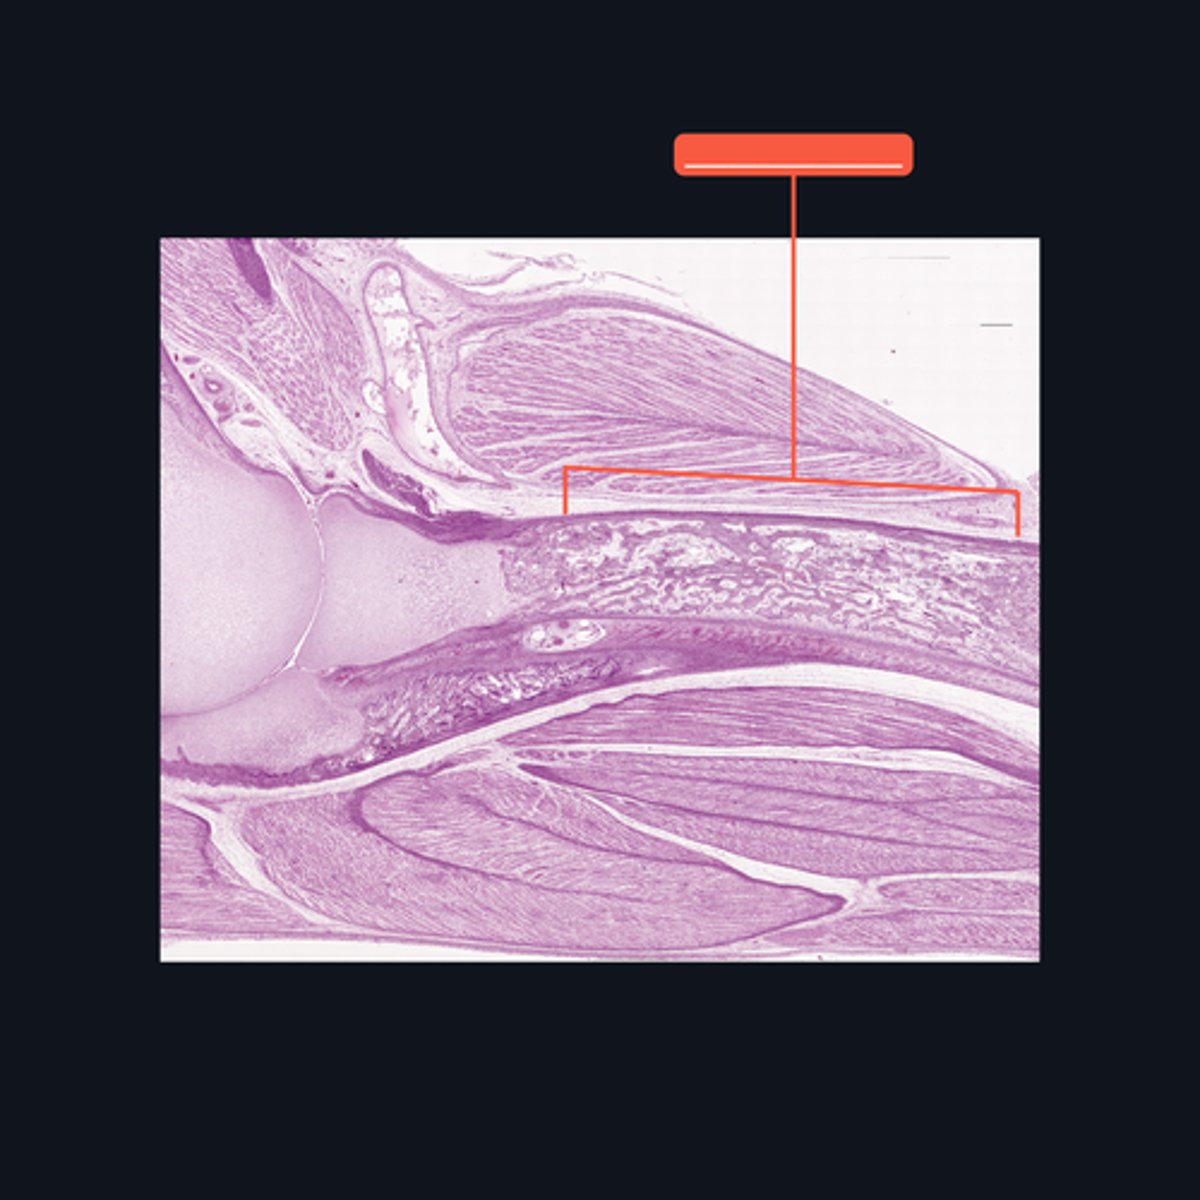

Diaphysis; shaft

Identify what part of a typical long bone is encompassed by the bracket symbol. It is also known as the _____ of a long bone.